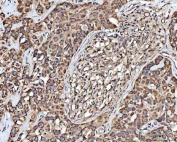

IHC staining of FFPE human parotid acinar cell carcinoma tissue with MECR antibody. HIER: boil tissue sections in pH8 EDTA for 20 min and allow to cool before testing.

IHC staining of FFPE human ovarian cancer tissue with MECR antibody. HIER: boil tissue sections in pH8 EDTA for 20 min and allow to cool before testing.

IHC staining of FFPE human liver cancer tissue with MECR antibody. HIER: boil tissue sections in pH8 EDTA for 20 min and allow to cool before testing.